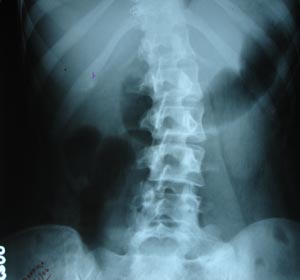

KUB & radio opaque calculas

Standard plain film of abdomen is in supine position. (when suspected of gas under diaphragm or to see air fluid level adv. Standing abdomen or erect film) Psoas outline is clearely visible. Kidney shadow is obscured by overlying colon. Look for any radio opaque shadow in the region of kidney, ureters or bladder. Faecolith should not be mistaken for renal or ureteric calculas.